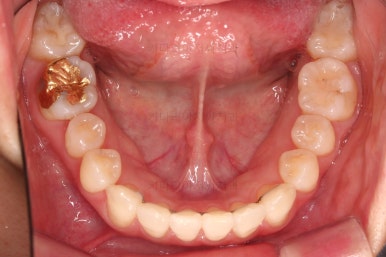

1. 초진

초진 시 입안의 모습입니다.

덧니가 눈에 띄고요.

맞물림이 긴밀하지 못한 상태였습니다.

전반적으로 약간 삐뚤지만 많이 심하다고 보긴 힘들었습니다.